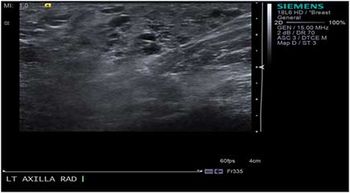

Case History: 29-year-old female, five days postpartum, presented with painful swelling and palpable lump.